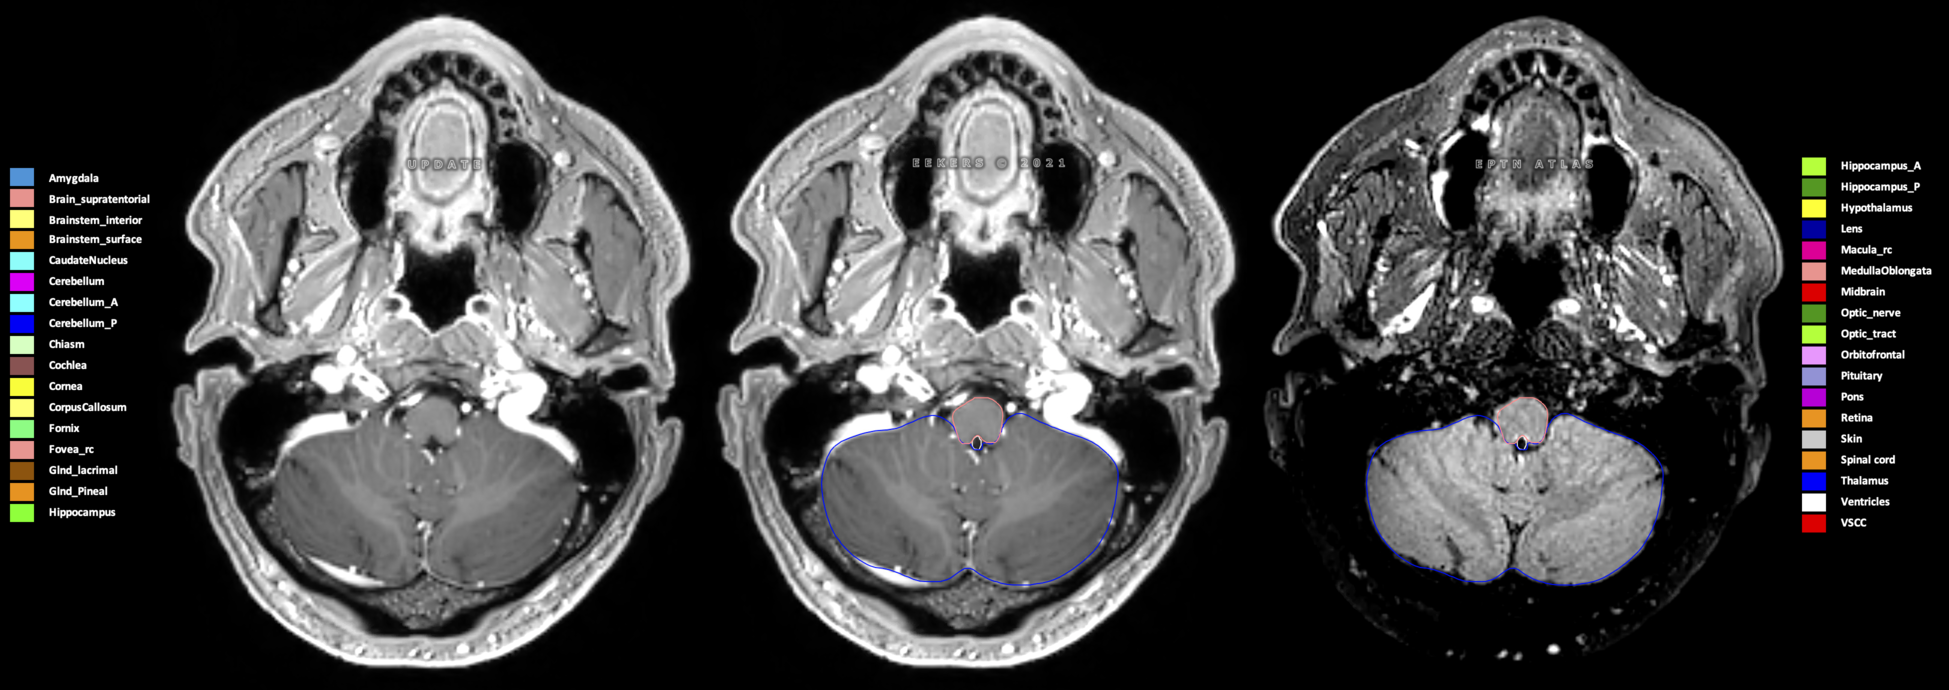

Eekers et al. have published an international neurological atlas for contouring of organs at risk in consensus with the European Particle Therapy Network (EPTN) in 2018 and an update in 2021. The purpose of this consensus atlas is to decrease inter- and intra-observer variability in delineating OARs relevant for neuro-oncology.

Included are all OARs known to be relevant for radiation-induced toxicity in neuro-oncology: brain, brainstem (midbrain, pons, medulla oblongata), chiasm, cerebellum (anterior & posterior), cochlea, cornea, hippocampus (anterior & posterior), hypothalamus, lens, lacrimal gland, optic nerve, pituitary, skin, and vestibular & semicircular canals. To further facilitate research on cognition, vision and radiological changes after irradiation of the brain, potential clinically-relevant OARs are included: amygdala, caudate nucleus, cerebellum (anterior & posterior), corpus callosum, fornix, macula, optic tract, orbitofrontal cortex, periventricular space (PVS), pineal gland, and thalamus.

Three-dimensional delineation of the 25 consensus OARs for neuro-oncology are shown on CT (WW/WL 120/40, 3000/600), 3T MR images, (T1Gd, T2FLAIR 1mm) and 7T MR (MP2RAGE 0.7 mm). All are presented in transversal, sagittal and coronal view.